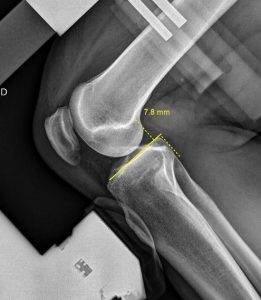

Le Telos Stress est un appareil permettant de réaliser les examens en salle de radiologie visant à tester la stabilité et quantifier la laxité des ligaments des  articulations.

Cet Appareil est particulièrement adapté à l’étude fonctionnelle des ligaments croisés des genoux LCA et LCP et ligaments collatéraux des chevilles avant toutes décisions thérapeutique ou chirurgicale.

Les mesures réalisées sur les images radiographiques permettent d’obtenir un diagnostic précis pour le prescripteur.